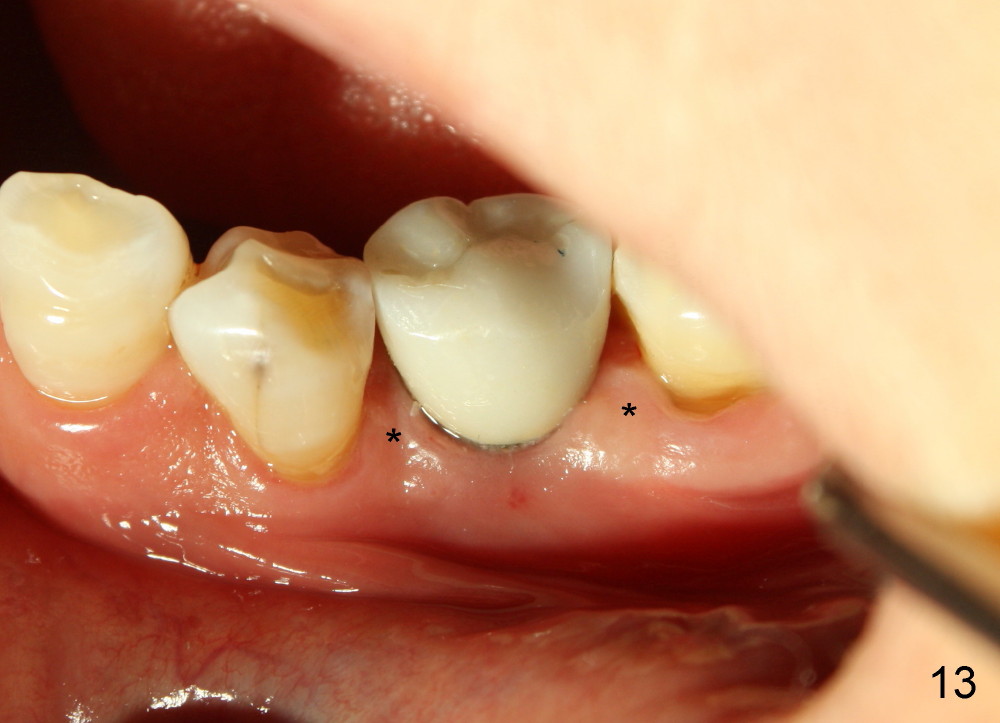

When the crown is bonded, the papillae (*) look basically normal lingually (Fig.12) and buccally (Fig.13).